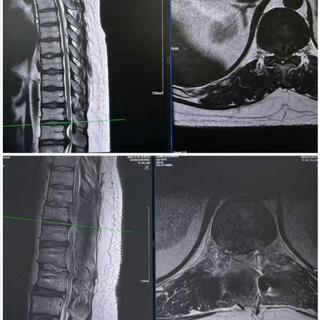

术后MRI见硬膜膨胀,脊髓减压充分

手术中,团队借助神经电生理监测仪全程护航,充分显露椎体后进行精准置钉、椎管减压、椎间盘切除、肋骨截骨、椎体整体前移等关键技术操作,历时4小时顺利完成手术,术后影像显示脊髓减压充分,次日,患者即感觉肢体麻木症状明显缓解。目前,小范术后恢复良好,自己感觉双腿明显轻松了,已能自主行走,下肢神经功能逐步恢复中。